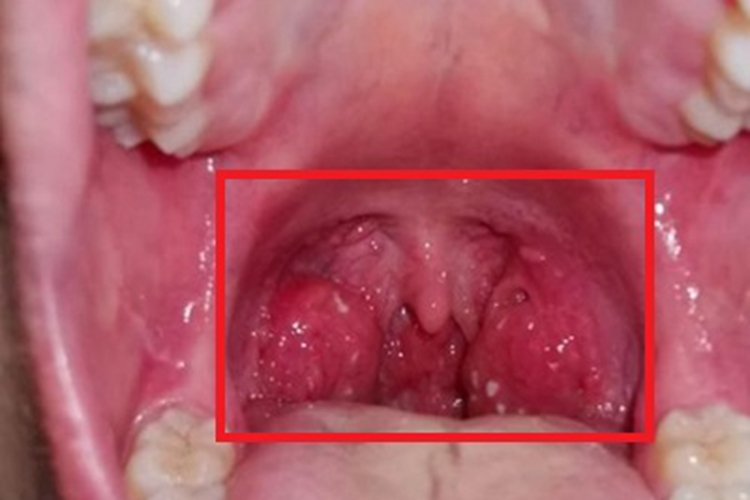

淋菌性咽炎患者在进行视诊时,可发现咽后壁出现异常,表现为黏膜表面充血、水肿,扁桃体附着有黄白色脓性分泌物,自觉有咽干、咽痛和吞咽痛等不适。